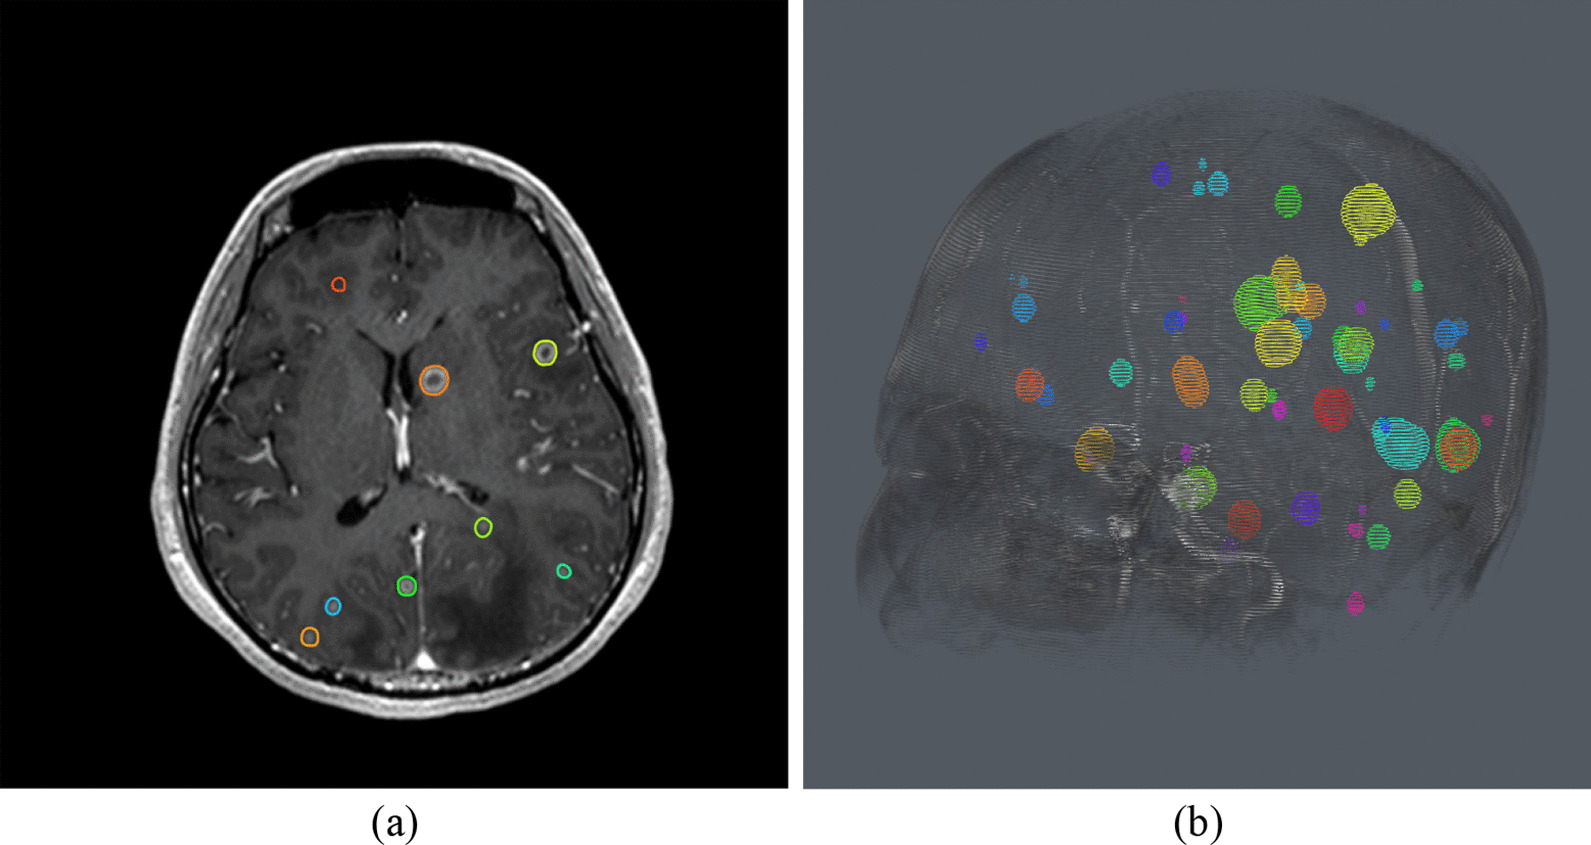

Figure 1 and Fig. 2 illustrate cases in which VBrain effectively predicted brain metastases among patients with numerous lesions (52) and lesions of small size (2.5 and 4.2 mm diameters). Figure 3 demonstrates challenging cases with tiny lesions, poor image quality, or insufficient contrast in the MR scan for which diagnostic reports and/or longitudinal images might be required for additional reference. No other statistically significant differences in performance metrics were observed across demographic and clinical characteristic groups.

Fig. 1.

Case with 52 Lesions. a Axial view. b 3D view. VBrain successfully predicted multiple brain metastases for this patient case with over 50 brain metastases, as this case had a Dice similarity coefficient (DSC) of 0.813, average Hausdorff distance (AVD) of 3.81% (0.511 mm), false positive count (FP) of 0, and sensitivity (%) of 90% and 100% for overall and > = 5 mm tumors, respectively